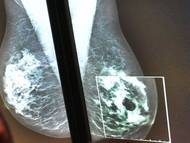

Rakovina je druhou nejčastější příčinou úmrtí v Evropské unii po onemocněních oběhové soustavy; nejčastěji na ni umírají lidé, kteří mají nádory plic. Vyplývá to z tiskové zprávy, kterou dnes vydala Evropská komise. Ta společně s Organizací pro hospodářskou spolupráci a rozvoj (OECD) představila onkologické profily jednotlivých unijních zemí a také Norska a Islandu. Vyplývá z nich, že v Česku je vysoký odhadovaný počet nových nádorových onemocnění a úmrtnost na ně je vyšší než průměr EU, nicméně klesá.